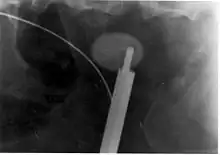

![]() Cálculo renal de oxalato de calcio | ||